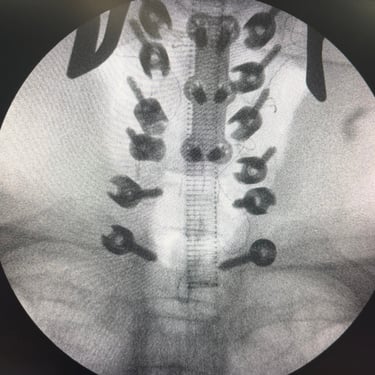

🧠 Fractura Vertebral Lumbar: Estabilización Segura con Fijación Transpedicular (FTP).

La fractura vertebral lumbar genera inestabilidad y dolor severo. La artrodesis con fijación transpedicular es una técnica quirúrgica eficaz que estabiliza la columna, previene desplazamientos vertebrales y mejora la recuperación funcional del paciente.